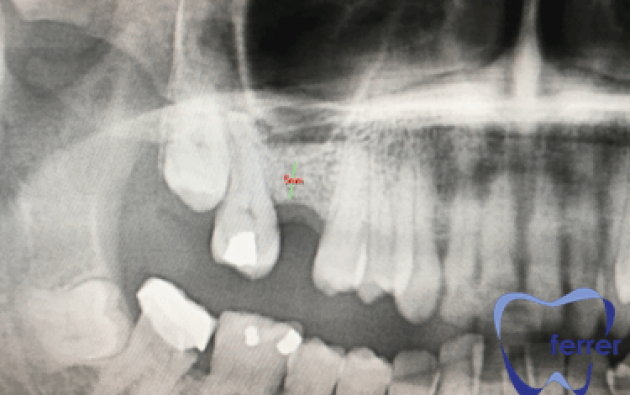

Durante esta valoración inicial, realizamos un escáner 3D o TAC dental de alta precisión que nos permite observar en detalle la cantidad y calidad del hueso disponible.

Esta imagen tridimensional nos ayuda a planificar el injerto con total seguridad, definiendo el volumen necesario y localizando estructuras anatómicas importantes como el nervio dentario o el seno maxilar.

Todo comienza con una primera consulta en la que realizamos pruebas y analizamos la zona para ver la cantidad de injerto que se va a necesitar y determinamos con el paciente cómo será el proceso que seguiremos.